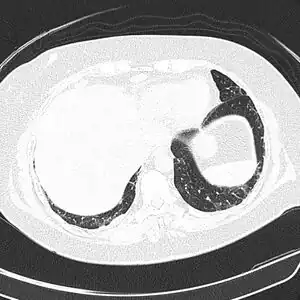

![]() ![]() text: From left to right: Cryptococcosis lung, cryptococcosis brain | |

CT scan lungs: mass in right upper lobe -